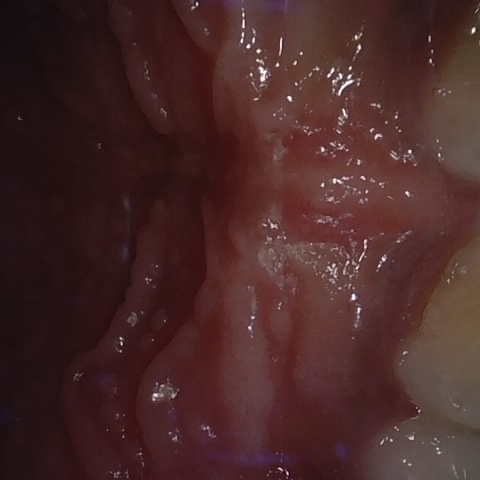

Annotated as "Good"